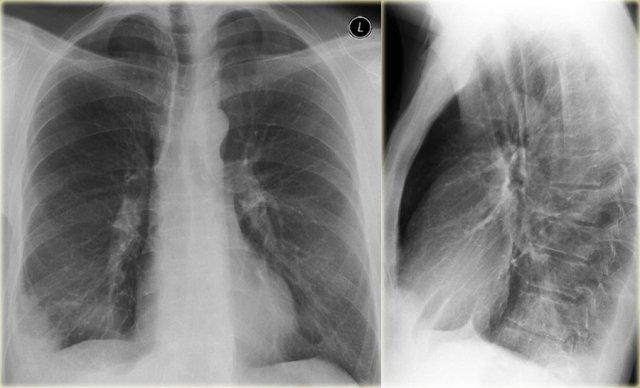

Xẹp thùy giữa phổi phải

Hãy quan sát kỹ các hình X-quang trước, sau đó tiếp tục đọc.

Các dấu hiệu là gì?

- Xóa mờ bờ tim phải (dấu hiệu bóng mờ)

- Đám mờ hình tam giác trên phim nghiêng do xẹp thùy giữa

Thông thường, xẹp thùy giữa phổi phải không gây nâng cao cơ hoành phải đáng kể.

Ngực lõm (pectus excavatum) có thể bắt chước hình ảnh xẹp thùy giữa trên phim thẳng, nhưng phim nghiêng sẽ giúp phân biệt được vấn đề này.